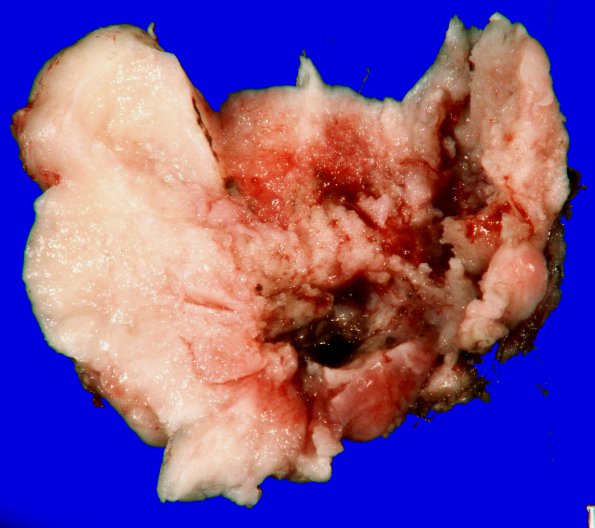

Washington University Experience | NEOPLASMS (MENINGIOMA) | Gross Pathology | 20B2 Meningioma, intraventricular (Case 20) _2

The gross tumor specimen shows mostly solid tumor areas on cut section (20B2,3), most of the hemorrhage is likely surgical in origin.